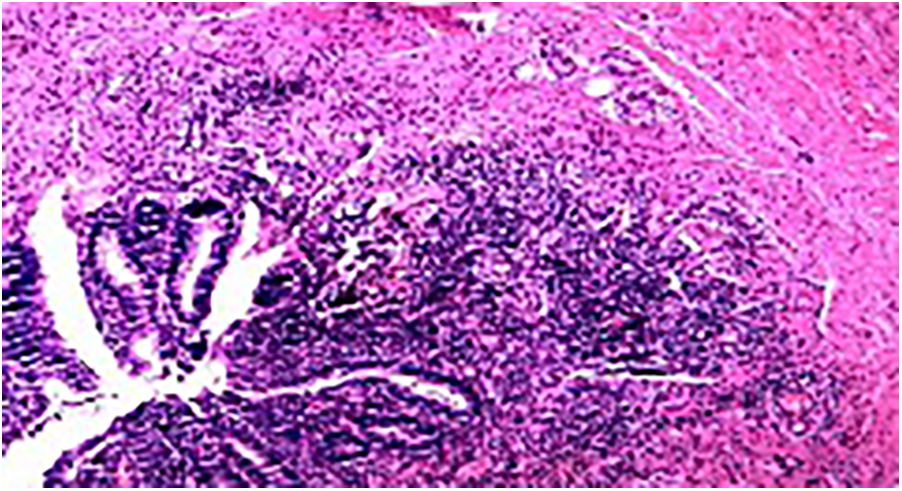

Postoperative pathology: Acute simple appendicitis, periappendicitis, and reactive hyperplasia of the surrounding lymph nodes (one piece) (Figure 3).

Figure 3

Pathological results of the appendix (H&E staining).